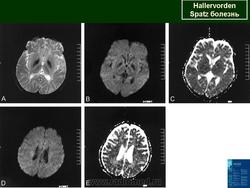

Галлервордена - Шпатца болезнь (J. Hallervorden, 1882-1965, нем. невропатолог; H. Spatz, совр. нем. невропатолог; син. ригидность прогрессирующая) - наследственная болезнь, связанная с нарушением обмена железа и липидов, проявляющаяся в возрасте 7-9 лет повышением мышечного тонуса, гиперкинезами, прогрессирующей деменцией, снижением зрения и пигментным ретинитом; наследуется по аутосомно-рецессивному типу.

Болезнь Галлервордена - Шпатца - наследственное заболевание экстрапирамидной системы, связанная с нарушением обмена железа и липидов и повреждением бледного шара и черной субстанции. Тип наследования аутосомно-рецессивный. При патоморфологическом исследовании характерным признаком является гиперпигментация бледного шара и черной субстанции. Обнаруживается пигментация коры полушарий большого мозга и таламуса. Пигмент находится внутри невронов и глиальных клеток, расположенных около сосудов; содержит железо (вместе с тем каких-либо нарушений обмена железа в организме не обнаружено). Наблюдаются утолщение и фрагментация аксонцилиндров в пораженных областях. Постепенно наступает дегенерация невронов коры полушарий большого мозга и мозжечка. Характеризуются нарастающей экстрапирамидной ригидностью, гиперкинезами (атетоз, торсионная дистония), затем развивается акинетико-ригидный синдром, пирамидная микросимптоматика, снижение интеллекта. Течение медленно прогрессирующее на протяжении 10 - 20 лет.

Клиническая картина. Заболевание начинается с прогрессирующего нарушения походки и ригидности в ногах, замедления и уменьшения объема произвольных движений, дизартрии и задержки умственного развития. У 50 % больных появляются хореиформные и атетоидные движения. Постепенно развиваются спастичность и атрофия дистальных отделов конечностей, признаки деменции. У больных нередко обнаруживают пигментный ретинит или атрофию зрительных нервов. Прогноз неблагоприятный.

"Глаз тигра"-наглядно и красиво.

Вы правы. Выставил еще более нагладные исллюстрации.